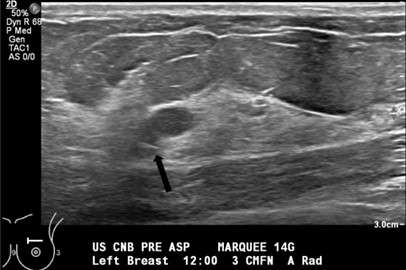

- Technologist saves an image documenting placement of the needle tip (Figure 2).

Figure 2. Grayscale sonogram shows the aspiration needle tip (black arrow) within the more posterior cystic structure.